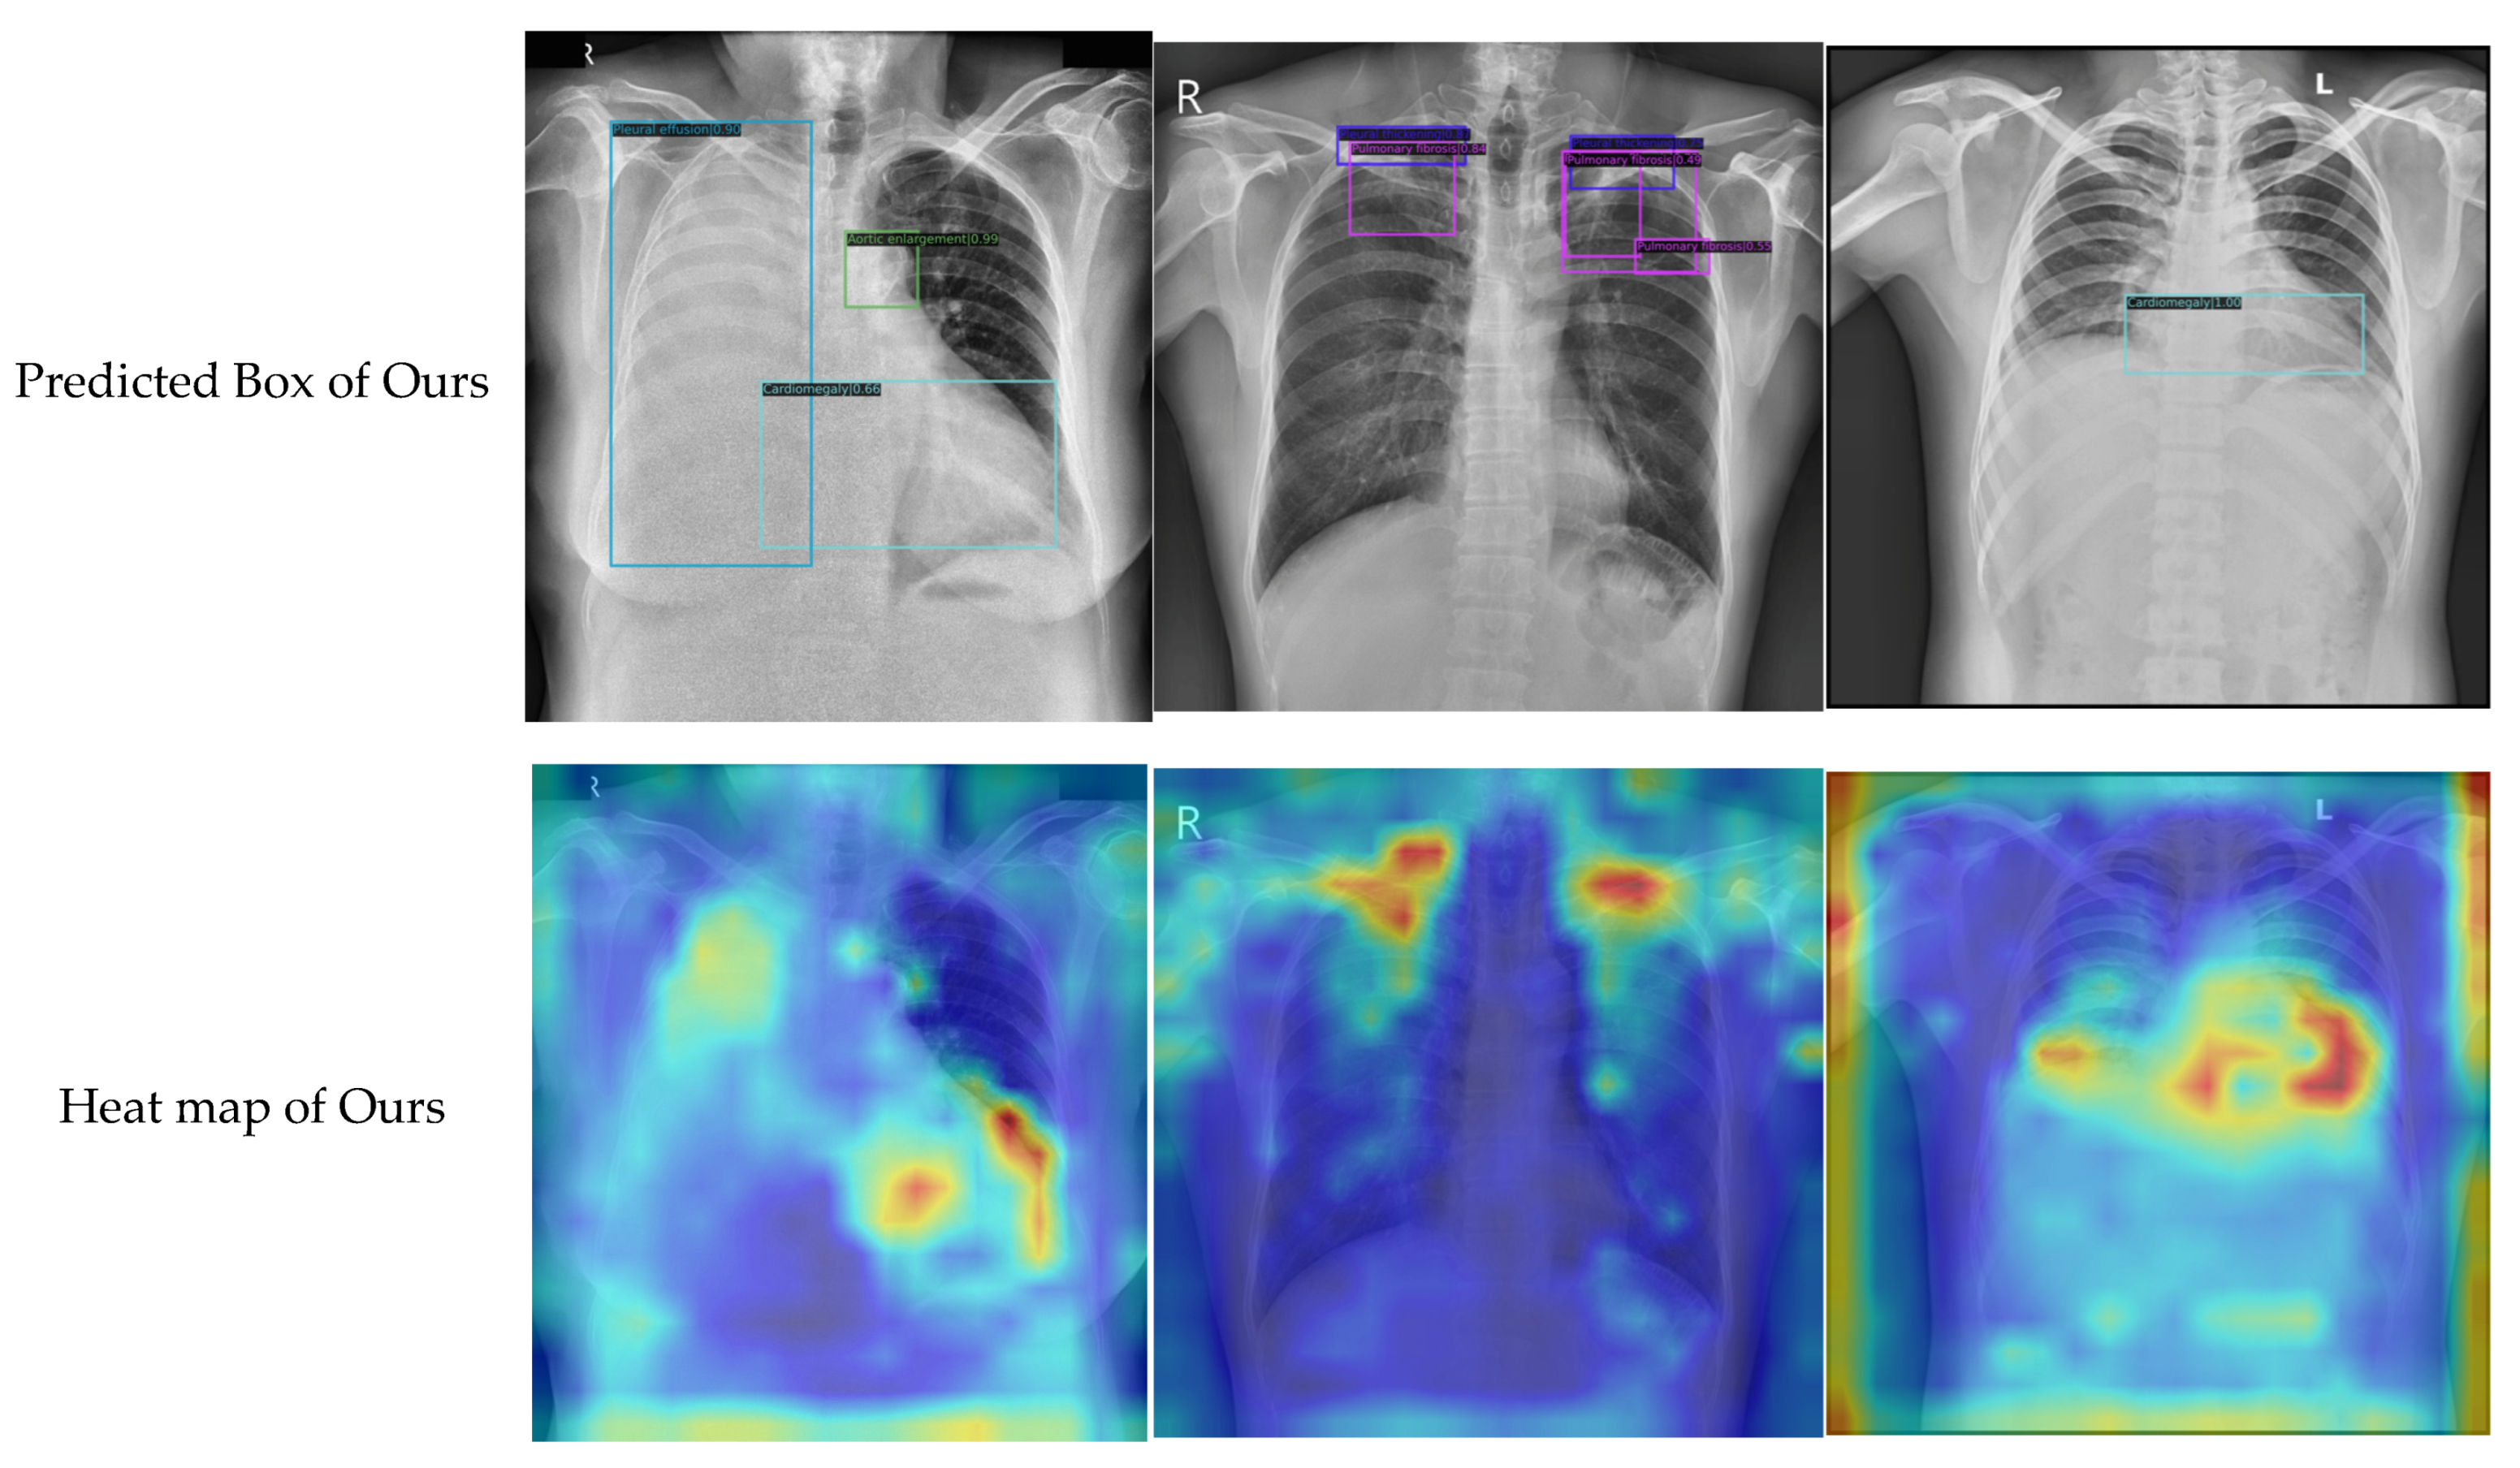

Figure 8.

Detection examples of the compared methods.

First, the proposed method achieved the highest mAP of 0.362, which was 3.2% higher than that of cascade R-CNN (baseline) and 4.8%, 5.6%, 11.3%, and 2.6% higher than that of TridentNet, Libra R-CNN, Sparse R-CNN, and Swin Transformer, respectively. Second, different models were suitable for different types of chest anomaly detection, but our model achieved the highest AP in most categories; that is, we achieved the best performance in five out of the fourteen categories. For example, Libra R-CNN achieved a superior detection precision in pleural effusion, whereas Sparse R-CNN was suitable for detecting large-scale chest abnormalities such as aortic enlargement. Another recently published method that has to be mentioned is Swin Transformer, which showed good potential in the anomaly detection of chest X-rays and achieved the highest AP in three categories, i.e., calcification, pneumo-thorax, and pulmonary fibrosis. However, the proposed method achieved the best results in most categories, including large-scale and small-scale abnormalities, such as infiltration, atelectasis, pleural thickening, consolidation, and cardiomegaly.

Second, by observing the anomaly detection examples shown in Figure 8, visual comparisons also proved that the proposed method generally achieved more accurate detection results, and that our approach could effectively identify the specific locations of various types of chest anomalies. Even for small targets, our method exhibited a high degree of coincidence with the ground truth. This was mainly due to the fact that we improved the backbone networks with embedded local features and context information. Moreover, with the optimized feature fusion process, information from different scales was rationally used to obtain a more accurate prediction region.

Finally, to carry out an interpretative analysis of our model, we used Grad-CAM [13] to generate a heat map visualization. Some representative examples of our model and the baseline are presented in Figure 10. By analyzing the results, the following conclusions could be drawn. First, compared with the baseline, the heat map generated by our model was more consistent with the ground truth. Second, the results of our qualitative prediction box also showed a certain correspondence with the heat map. This implied that Grad-CAM had a certain faithfulness to our model, and that the proposed method had good reliability. In general, the heat map produced with our method highlighted the discriminative regions that were more consistent with the visual judgment of radiologists, although it must be noted that this method of comparison was a relatively subjective way of evaluating the proposed method.

Figure 10.

The heat map visualization for proposed model and baseline.